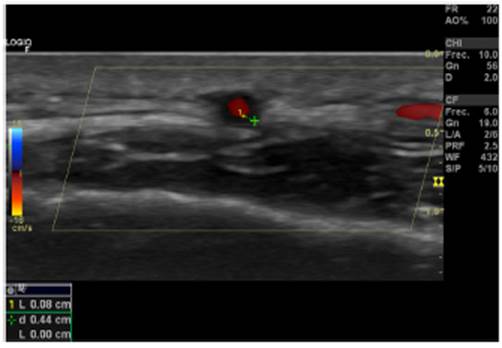

Signo del halo (fig. 2): es un engrosamiento homogéneo de la pared, hipoecoico (en el modo B), de bordes definidos (se logra delimitar el tejido adyacente al vaso), visible en el plano transverso (usualmente concéntrico) y longitudinal. Refleja el edema de la pared del vaso y es el hallazgo más relevante para esta enfermedad. Algunos estudios definieron puntos de corte del diámetro del halo para arterias temporales entre 0,3 y 1,0 mm y para arterias axilares entre 1,0 y 2,0mm19,20. Schafer et al., en un estudio prospectivo de 40 pacientes con ACG comparados con controles sanos, encontraron que el diámetro del grosor íntima-media (GIM) normal era en promedio de 0,2 mm en arterias temporales y de 0,6 mm en arterias axilares, y establecieron puntos de corte para el GIM de los pacientes con ACG en las arterias temporales superficiales comunes de 0,65 mm (sensibilidad y especificidad del 100%), en la rama frontal de 0,54mm (sensibilidad y especificidad del 100%), en la rama parietal de 0,50 mm (sensibilidad del 97,2% y especificidad del 98,7%), en la arteria facial de 0,53 mm (sensibilidad del 87,5% y especificidad del 98,8%) y en las arterias axilares de 1,7 mm (sensibilidad y especificidad del 100%)21. Varios metaanálisis han reportado una sensibilidad del 68-77% y especificidad del 83-96% para el signo del halo unilateral y una sensibilidad del 43% y especificidad del 100% para el signo del halo bilateral22-25, con un valor predictivo positivo del 50% y un valor predictivo negativo del 96%26. La sensibilidad del ultrasonido Doppler solo se incrementa en un 2% cuando se adiciona la evaluación de las arterias axilares al estudio de las arterias temporales27. Diferentes estudios han mostrado que en la mayoría de los pacientes el signo del halo no es visible luego de 2-4 semanas después del inicio de la terapia con glucocorticoides, debido a que los cambios inflamatorios desaparecen y la sensibilidad del estudio disminuye al 50% a partir del 4.° día de tratamiento, por lo que se recomienda la evaluación temprana con el ultrasonido Doppler en los primeros 2 días después del inicio del tratamiento28-30.

Signo de compresibilidad de la arteria temporal (fig. 3): es la persistencia del halo hipoecoico a pesar de la compresión extrínseca de la luz arterial con el transductor de ultrasonido («signo de compresibilidad»); es una variante del halo con una sensibilidad del 77-79% y una especificidad del 100%31,32.